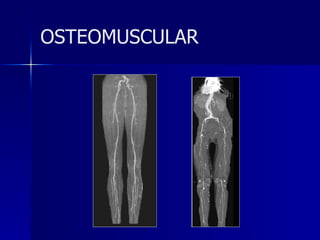

Osteomuscular Mayor velocidad Mayor Resoluciòn Capacidad multiplanar Imagen volumetrica

Multicorte Ortopedia